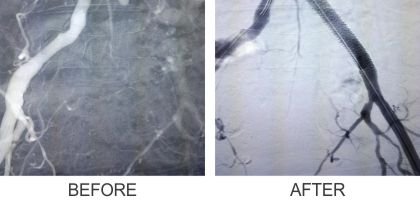

2. Iliac Angioplasty

6. Subclavian Angioplasty